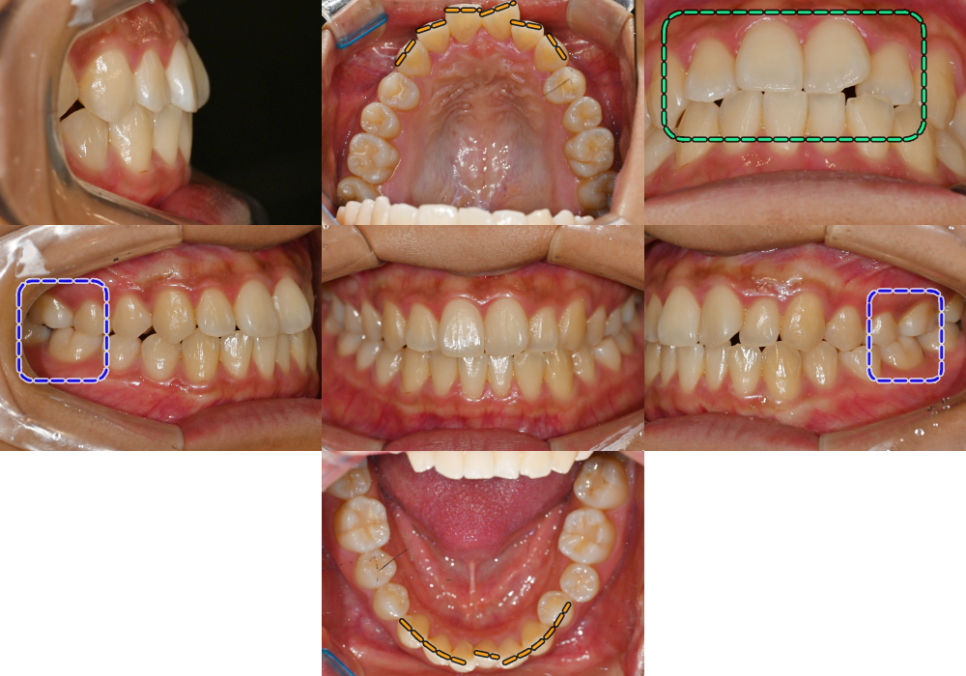

구강 내 모습을 먼저 보겠습니다.

먼저 위아래 치열이 삐뚤고,

윗니가 아랫니를 안정적으로 덮지 못하고

절단연 교합인 것을 확인할 수 있습니다.

더불어, 양쪽 어금니가

3급 부정교합이었는데요.